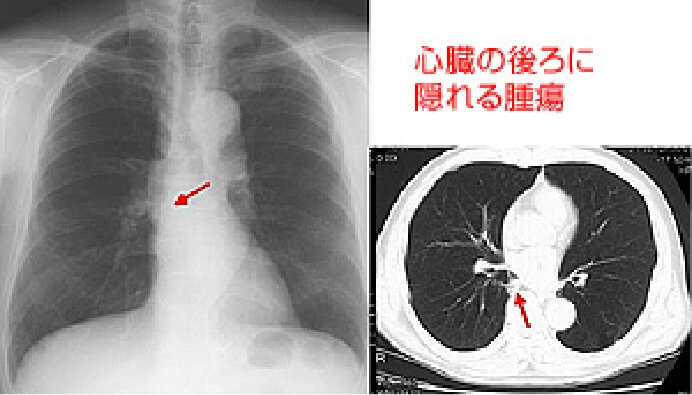

おもに呼吸器(気管・肺など)、循環器(心臓)などに病気があるかどうかを調べるための検査です。肺がん・じん肺・肺結核・肺炎・気胸・胸水・心拡大などの診断に有用です。しかし、小さな肺がんは検出されないことがあるため(症例画像参照)、喀痰細胞診検査・胸部CT検査をあわせておこないます。

肺・気管・気管支などを輪切り(断面)の状態で撮影し、小さい病変を見つける検査です。早期肺がんの診断はもちろんのこと、「低線量CT装置」を用いることにより、X線写真では発見しにくい中心型(肺門型)肺がんも検出することができます。(症例画像参照)

単純X線写真で発見困難な症例2